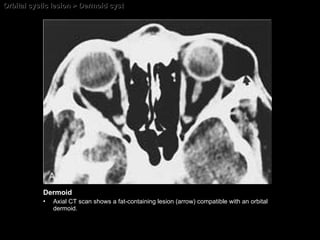

CT AND MR IMAGING FEATURES Intensity of adipose tissue Density of adipose tissue Dermolipoma HypoSI on T1WI and hyperSI on T2WI Fatty tissue Minimal enh of capsule may be present Associated orbital inflammatory changes, when cyst is ruptured Non-enh mass with or without bone erosion Calcification, if present, is a characteristic feature fat, if present, is characteristic  Scalloping with sclerosis of the adjacent bone may be present Minimal enh of the capsule may be present Dermoid cyst HypoSI on T1WI and hyperSI on T2WI Minimal enh of capsule may be present Associated orbital inflammatory changes, when cyst is ruptured Non-enh mass with or without bone erosion No calcification Scalloping with sclerosis of the adjacent bone may be present Minimal enh of the capsule may be present Epidermoid cyst MRI CT

Orbital cystic lesion > Dermoid cyst Dermoid Axial CT scan shows a fat-containing lesion (arrow) compatible with an orbital dermoid.